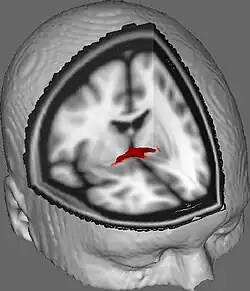

![]() Coronal cross-section of brain showing the anterior commissure. (left, third from bottom.) | |

The anterior commissure (also known as the precommissure) is a white matter tract (a bundle of axons) connecting the two temporal lobes of the cerebral hemispheres across the midline, and placed in front of the columns of the fornix. In all but five species of mammal the great majority of fibers connecting the two hemispheres travel through the corpus callosum, which in humans and all non-monotremes is more than 10 times larger than the anterior commissure. Other routes of communication pass through the hippocampal commissure or, indirectly, via subcortical connections. Nevertheless, the anterior commissure is a significant pathway that can be clearly distinguished in the brains of all mammals.

In a sagittal section, the anterior commissure is oval in shape, having a long vertical axis that measures about 5 mm.